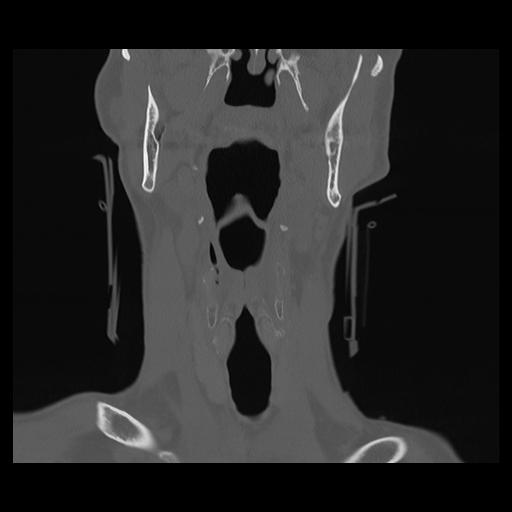

16 HUESO,,Coronal,2.000,HUESO,Coronal,